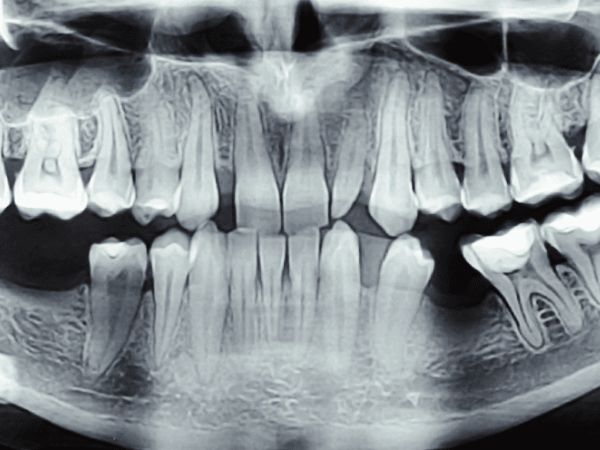

We use state-of-the-art digital radiography and cone beam computed tomography (CBCT) to produce detailed, high-resolution images of teeth, bone, nerves, and surrounding structures — instantly and with up to 90% less radiation than traditional film X-rays. Digital images are displayed chairside in seconds, allowing your dentist to discuss findings with you in real time.

Our 3D CBCT scanner provides a full volumetric view of the jaws and skull, which is invaluable for implant planning, assessing impacted teeth, diagnosing complex root canal anatomy, evaluating bone volume before surgery, and detecting pathologies that 2D X-rays may miss. This technology leads directly to better-planned, safer, and more predictable treatments.

Digital X-rays or a CBCT scan are taken in a matter of seconds. The process is completely painless — you simply bite on a small sensor or stand in position for the scanner. Images appear on screen immediately.

Your dentist reviews the images with you chairside, explaining exactly what they show in plain language. Intraoral camera images may also be shared to give you a complete picture of your dental health.

High-resolution imaging detects decay between teeth, bone loss, cysts, and root problems at an early stage when treatment is simpler and less costly.